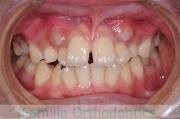

歯並びを治したいということで来院されました。下あごがやや右側に偏位して後退している、上顎前突(出っ歯)でした。上下左右から小臼歯を抜歯して、歯科矯正用アンカースクリューを併用したマルチブラケット法にて治療を行いました。約2年、24回の来院をしていただきました。

下顎の後退はいびきなどの上部気道の障害が出やすいと考えられます。